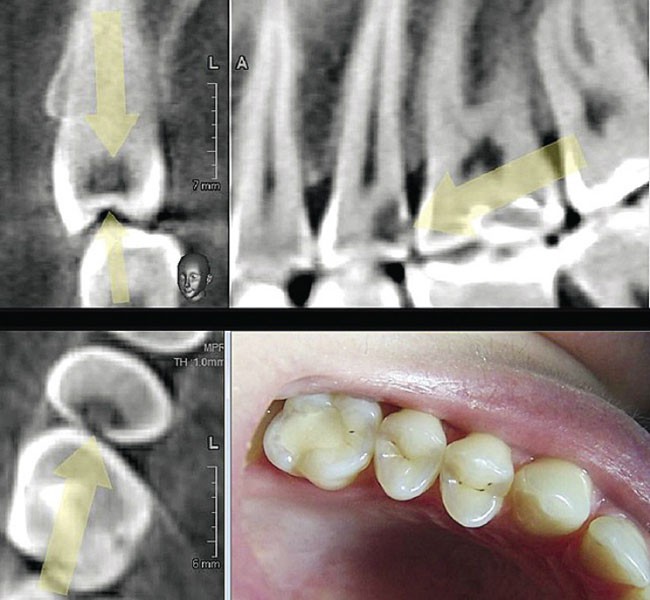

Традиционные методы диагностики окклюзионных нарушений, такие как гипсовые модели и рентгенография, обладают определенными ограничениями․ Гипсовые модели, хотя и являются важной частью диагностического процесса, не всегда позволяют точно передать все нюансы прикуса, особенно в сложных случаях․ Рентгенография предоставляет информацию о костной ткани, но не дает полного представления о взаимоотношении зубов в трехмерном пространстве․ 3D-моделирование же позволяет преодолеть эти ограничения, предоставляя стоматологам полную и точную картину анатомических структур и их взаимосвязи․

Процесс диагностики окклюзионных нарушений с помощью 3D-моделирования включает несколько этапов․ Сначала проводится сканирование челюстей пациента с помощью внутриротового сканера․ Этот сканер создает высокоточное цифровое изображение челюстей и зубов․ Далее, полученные данные обрабатываются специальным программным обеспечением, которое создает трехмерную модель․ На основе этой модели врач проводит анализ прикуса, выявляя все существующие отклонения․